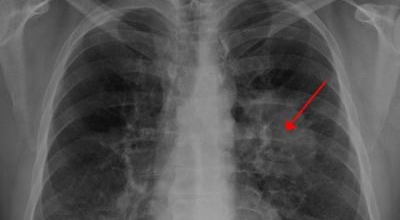

폐에 발생된 악성 종양을 말하며 오랜 기간 흡연해온 남성들에서 발병률이 높고 최근에는 각종 환경적인 요인의 영향과 간접흡연으로 흡연하지 않는 여성에서도 많이 발생하고 있습니다. 증상을 느껴 병원을 찾았을 때는 수술하기 늦은 경우가 많아 사망률이 매우 높은 암입니다. 폐 자체에서 발생하거나 다른 장기에서 발생된 암이 폐로 전이되어 발생하기도 하고 특별한 초기 증상이 없는 경우가 많고 암이 진행된 후에도 동일한 감기 증상인 기침과 가래 외의 특이 증상이 나타나지않아 증상만으로는 진단이 쉽지 않습니다.